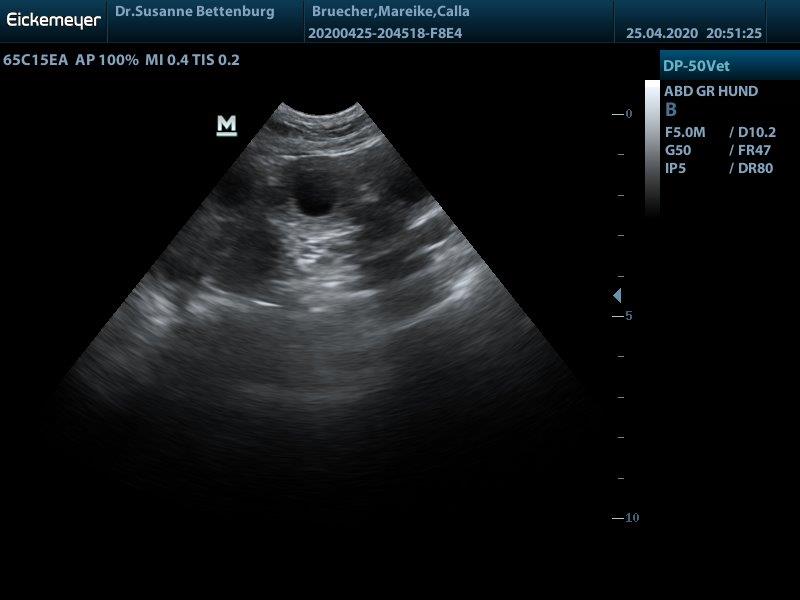

Juhuu Calla ist trächtig!!!!! wir haben viele kleine Baby's gesehen und erwarten anfang Juni einen großen Wurf

bei Intresse an einem Welpen aus dieser tollen Verpaarung melden sie sich bitte unter der Telefonnr. 05143/93495 oder 0172/4410385 oder schreiben Sie mir an melbys@live.de

Hurra hurra der E-Wurf ensteht

"Calla" Stoneyard's dark velvet New style wurde am 03.04.2020

von "Leo" Erix One to one gedeckt. So dass wir die Welpen wenn alles gut geht um den 02.06.2020 erwarten